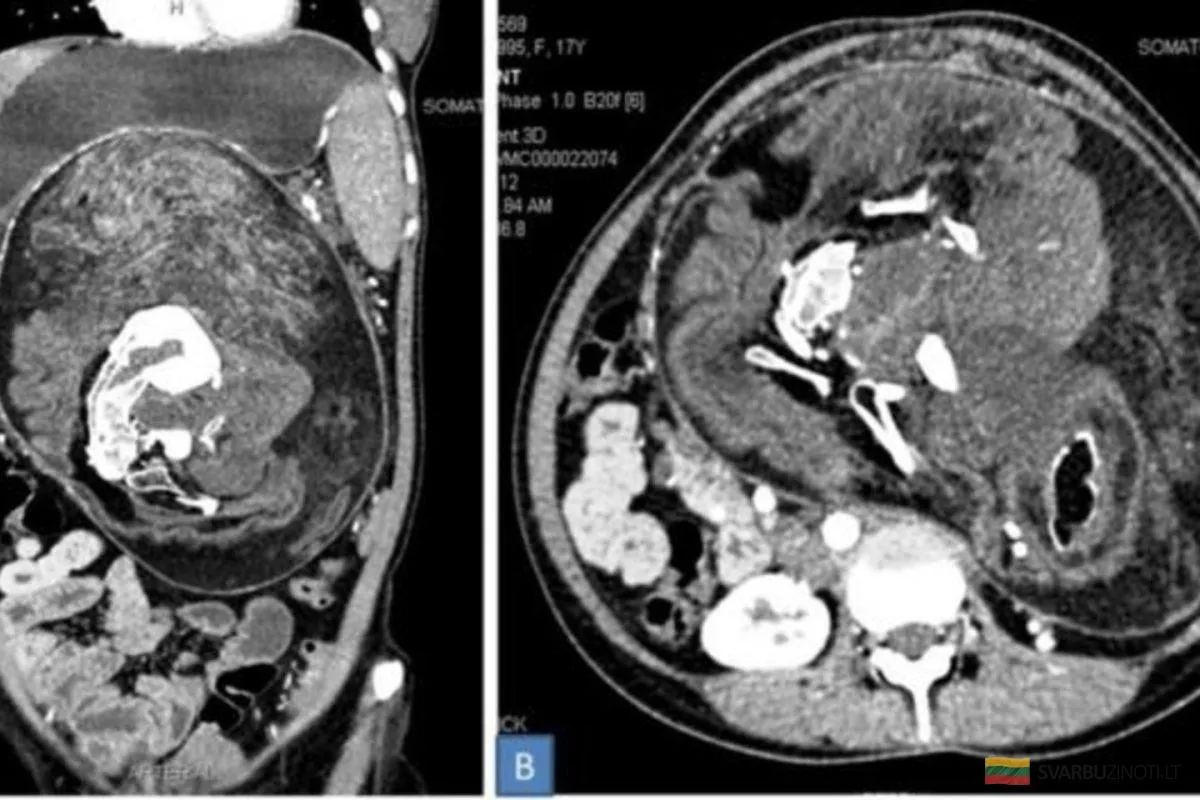

Онкологические заболевания

КТ важен для диагностики и наблюдения за онкологическими заболеваниями. Например, при:

Раке легких

Раке печени

Опухолях других органов

КТ помогает оценить размер опухоли и ее реакцию на лечение.

КТ органов брюшной полости и малого таза помогает диагностировать заболевания печени, почек и поджелудочной железы. Этот метод выявляет опухоли и кисты.